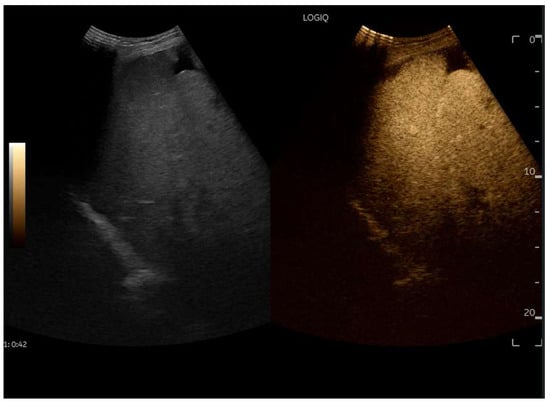

CEUS is valuable for characterizing the contrast enhancement patterns of liver nodules [68,69,70,71]. In Europe, the US contrast agent SonoVue® (sulfur hexafluoride; Bracco, Milan, Italy) is approved only for intravenous applications in patients over 18 years of age [72]. CEUS use in Fontan patients remains limited due to their frequent collateral circulation with right-to-left shunts, which is considered a contraindication in Europe but not in the United States. Beyond structural liver changes, CEUS reveals markedly heterogeneous hepatic enhancement with mosaic or reticular patterns, mainly due to slow and reduced enhancement near congested hepatic veins—one of the most common imaging features of FALD [54,73]. Anecdotal experience suggests that CEUS demonstrates heterogeneous and decreased liver enhancement in the portal venous phase, similar to cirrhosis of other etiologies (Figure 14, Figure 15). Abnormal enhancement is more prominent at the liver periphery than centrally, while the hypertrophic caudate lobe often shows more homogeneous enhancement. In patients with FALD, the altered hemodynamics resulting from chronic hepatic venous congestion and low cardiac output can significantly influence CEUS dynamics. Despite these circulatory changes, CEUS in FALD generally preserves the standard temporal enhancement pattern. The hepatic veins, although congested, do not typically show early enhancement, as microbubble distribution primarily reflects arterial input. The systemic hypokinetic circulation characteristic of FALD may lead to delayed arterial arrival times and a prolonged transit of contrast, especially in the background of the liver. Nonetheless, FNH-like nodules frequently exhibit intense and early arterial-phase hyperenhancement, suggesting preserved or increased arterial supply in these lesions. This contrast behavior is essential for lesion characterization.

Figure 14.

Contrast-enhanced ultrasound (CEUS) in the late phase shows the appearance of hypo-vascular areas due to varying degrees of congestion and hepatic alteration. These areas may mimic malignant nodular lesions with early washout.

Figure 15.

CEUS exam showing late heterogeneous enhancement in the arterial phase with evidence of hypo-enhanced areas, thus mimicking a malignant wash-out.